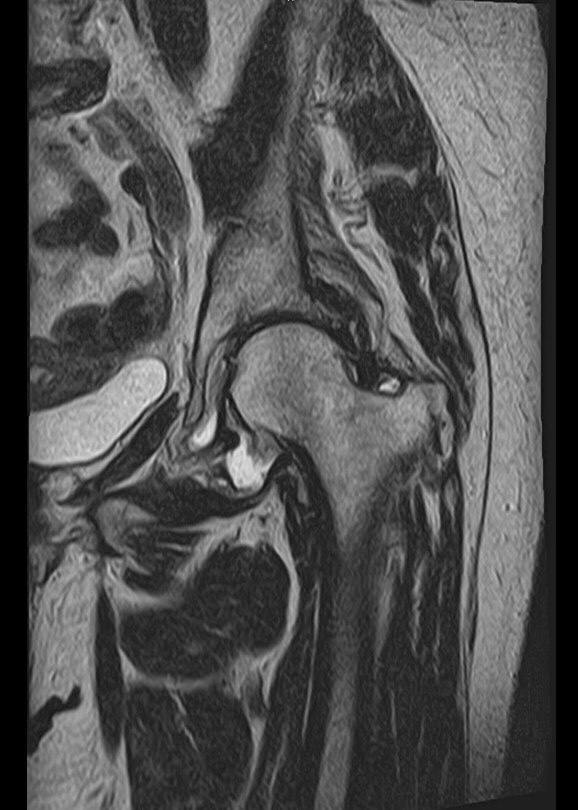

Магнитно-резонансная томография (МРТ) – это высокоточный метод диагностики, который позволяет получить детальные изображения костных и мягкотканевых структур без использования рентгеновского излучения. Расширенное МРТ тазобедренного сустава — это углубленный вариант исследования, включающий специальные протоколы, повышающие точность диагностики.

• Высокое разрешение изображений для оценки мельчайших повреждений

• Специальные режимы сканирования, включая 3D-реконструкцию